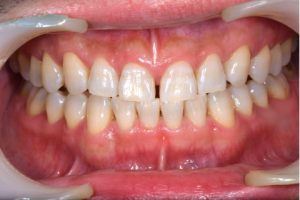

デュアルホワイトニング症例

治療前

治療後

年齢 30代女性

主訴 歯を白くしたい

治療

方針

オフィスホワイトニング

ホームホワイトニング

期間

6ヶ月(患者様の都合でゆっくり治療しました)

費用 カウンセリング 0円

55,000円(税込)